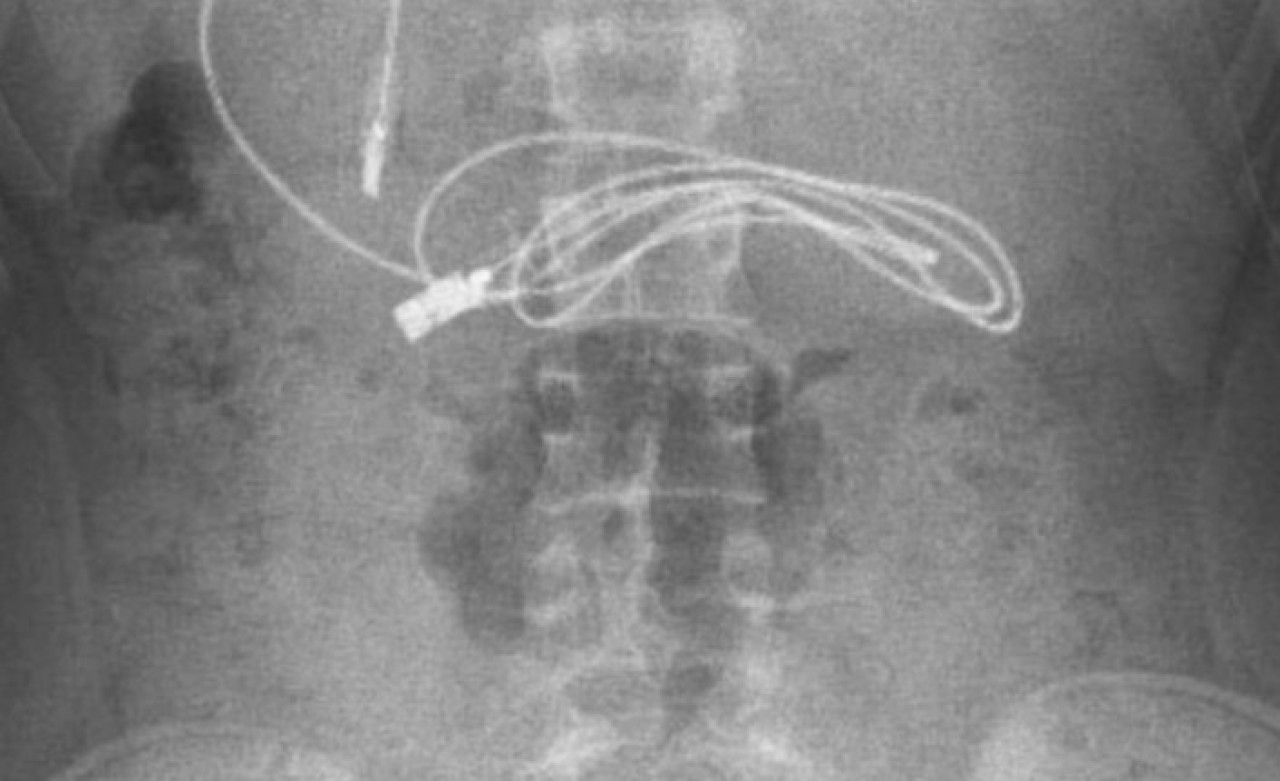

Diyarbakır'da kusma ve bulantı şikayetiyle hastaneye götürülen, çekilen röntgeninde 1 metrelik şarj kablosu ve toka yuttuğu tespit edilen 15 yaşındaki erkek çocuğu, Elazığ'da gerçekleştirilen operasyonla yuttuğu cisimlerden kurtuldu.

Diyarbakır'da kusma ve bulantı şikayetiyle ailesi tarafından hastaneye götürülen erkek çocuğunun çekilen röntgeninde, midesinde şarj kablosu ve toka olduğu tespit edildi. Bunun üzerine çocuk, ambulans ile Fırat Üniversitesi Hastanesi'ne sevk edildi.

Ameliyatı gerçekleştiren Prof. Dr. Yaşar Doğan, kablonun bir ucunun ince bağırsağa geçmesi nedeniyle zorlandıklarını ifade ederek, "Hastanın kusma ve karın ağrısı şikayetleri olması üzerine sağlık kuruluşuna başvurulmuş. Orada yapılan incelemelerde hastanın midesinde kablo tespit edilmesi üzerine bize danışıldı. 112 aracılığıyla hastaya gerekli işlemi yapıp yapmayacaklarını bize sordular. Biz de hastayı bize gönderebileceklerini kendilerine ilettik. Hasta bize geldikten sonra ön hazırlık yapıldı ve gerekli olan açlık süresinin ardından hastaya endoskopik işlem yapıldı.

Endoskopik işlemle midedeki kablo çıkarıldı. Kabloyu çıkarırken açıkçası zorlandık, çünkü kablonun bir ucu ince bağırsağa geçmişti. İşlem başarılı bir şekilde sonlandırıldıktan sonra hasta sağlıklı bir şekilde evine gönderildi" dedi.